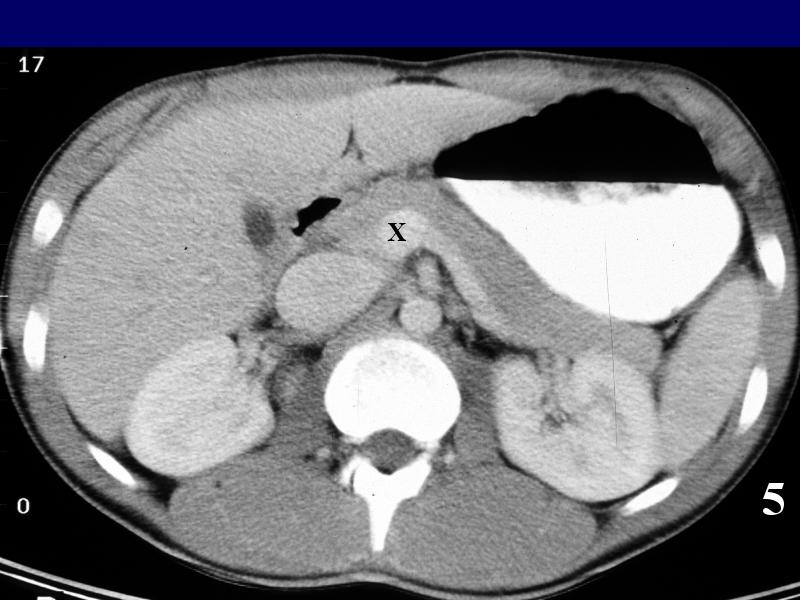

MS 190 CT 16